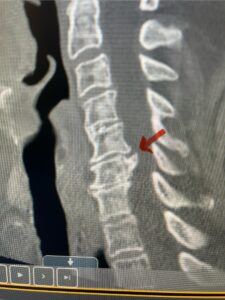

This 61-year-old female with a history of severe osteoporosis and a prior history of a laminectomy from l2-S1 with an L5-S1 instrumented fusion, presents with progressive low back pain and right lower extremity radiculopathy. MRI revealed a grade 1 L2-3 spondylolisthesis with severe stenosis mainly from severe right L2-3 facet joint hypertrophy which was compressing the right L3 descending nerve root. (Fig. 1). She had failed conservative management consisting of physical therapy and pain management with epidurals. She underwent an L1-3 revision laminectomy where we had to dissect a plane underneath the inferior aspect of the L2 lamina. We performed an instrumented fusion at L2-3 with special hydroxyapatite-coated screws to improve fixation to surrounding bone given here severe osteoporosis (Fig. 2) This worked out well and the patient had an uneventful recovery with relief of her leg pain.

Figures 1a: Sagittal and axial T2-weighted lumbar MRIs demonstrating a grade 1 L2-3 spondylolisthesis (red arrow) with severe stenosis secondary to right L2-3 facet hypertrophy (red arrow).